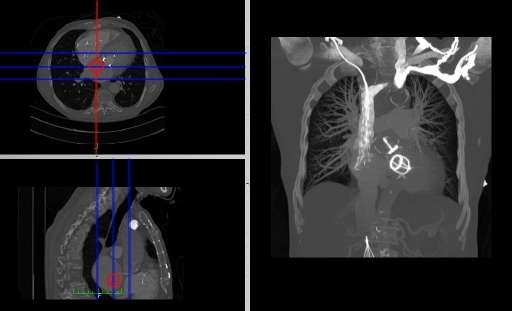

We'll conclude this chapter by considering an application of 3D visualization which integrates many of the image processing techniques we've described in this wikibook. We'll use the two SPECT scans, from a patient's lung-ventilation (V) and lung-perfusion (Q) studies, in an attempt to visualize any mismatch(es) characteristic of pulmonary embolism (PE). The application we'll consider is called subFusion Processing because it involves both image subtraction and image fusion techniques.

Note again that the SPECT studies were generated using a swamping technique where the perfusion scan was acquired immediately following the ventilation scan using an administered activity which generated a relative count rate of about 5:1 between scans. The first image processing step therefore is to correct the perfusion scan for the background ventilation activity.

Since the ventilation tracer in this case was administered using a aerosol, we can assume for simplicity that its biodistribution is reasonably identical in the two scans. Further, since the scans were acquired about 15 minutes apart using the 99mTc radioisotope, we can assume a neglegible effect from radioactive decay. We can simply therefore subtract the ventilation stack from the perfusion stack, on the basis of these assumptions, to isolate what we'll call the "pure perfusion" scan.

The second step is to normalize the two scans by multiplying the ventilation stack by a factor such that the mean counts (for example) in the two stacks are similar.

Since a PE mismatch is likely to arise from regions of the lungs which contain counts in the ventilation scan and are relatively bereft of such counts in the perfusion scan, we can subtract the "pure perfusion" stack from the ventilation stack, as a third image processing step, to isolate any such differences as positively-valued features.

The final image processing step is to volume render this difference stack along with the "pure perfusion" scan and to blend the results, as illustrated in the following image:

The steps involved are outlined in the following diagram. Note that minor processes, such as CLUT selection, relative opacity adjustment and contrast enhancement are omitted from this diagram for the sake of simplicity. Note also that an image registration step may need inclusion at the beginning of the procedure in cases where patient movement occurs between the two SPECT acquisitions.

A final point to note is the larger appearance of the patient's lungs in the segmented CTPA images relative to the SPECT images. This arises because the CTPA study was acquired using a single breath-hold and the SPECT studies with the patient breathing quietly over the period of gamma camera rotation. The spatial registration of the three sets of images is therefore not possible directly, and would require the application of spatial warping and other techniques which, unfortunately, are beyond the scope of our treatment here.